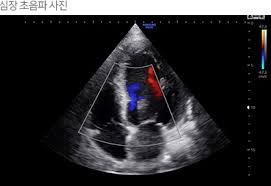

심장 초음파로 알 수 있는 병 ② 심장 판막 질환

심장에는 혈액의 흐름을 조절하는 판막이 존재합니다. 심장 초음파는 판막이 제대로 열리고 닫히는지, 역류가 있는지를 정확하게 보여줍니다.

- 승모판막 협착·폐쇄부전

- 대동맥판막 협착·역류

이처럼 판막 이상은 대표적인 심장 초음파로 알 수 있는 병에 해당하며, 심잡음이 들릴 때 필수적으로 시행됩니다.